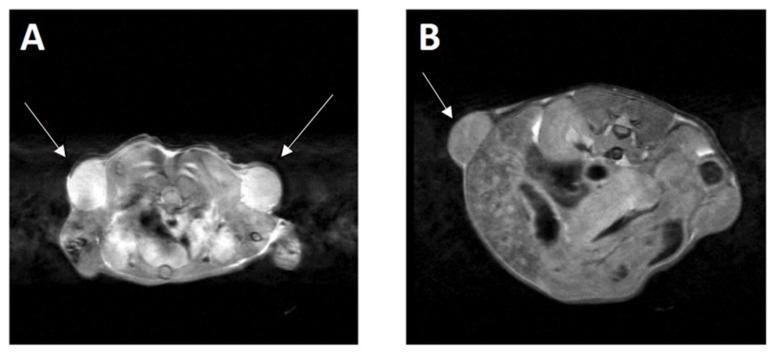

The B-cell CLL/lymphoma 11B gene (BCL11B) plays a crucial role in T-cell development, but its role in T-cell malignancies is still unclear. To study its role in the development of T-cell neoplasms, we generated an inducible BCL11B knockout in a murine T cell leukemia/lymphoma model. Mice, bearing human oncogenes TAL BHLH Transcription Factor 1 (TAL1; SCL) or LIM Domain Only 1 (LMO1), responsible for T-cell acute lymphoblastic leukemia (T-ALL) development, were crossed with BCL11B floxed and with CRE-ER/lox mice. The mice with a single oncogene BCL11Bflox/floxCREtg/tgTAL1tg or BCL11Bflox/floxCREtg/tgLMO1tg were healthy, bred normally, and were used to maintain the mice in culture. When crossed with each other, >90% of the double transgenic mice BCL11Bflox/floxCREtg/tgTAL1tgLMO1tg, within 3 to 6 months after birth, spontaneously developed T-cell leukemia/lymphoma. Upon administration of synthetic estrogen (tamoxifen), which binds to the estrogen receptor and activates the Cre recombinase, the BCL11B gene was knocked out by excision of its fourth exon from the genome. The mouse model of inducible BCL11B knockout we generated can be used to study the role of this gene in cancer development and the potential therapeutic effect of BCL11B inhibition in T-cell leukemia and lymphoma.

B 细胞慢性淋巴细胞白血病/淋巴瘤 11B 基因(BCL11B)在 T 细胞发育中发挥着关键作用,但它在 T 细胞恶性肿瘤中的作用尚不清楚。为了研究其在 T 细胞肿瘤发生中的作用,我们在小鼠 T 细胞白血病/淋巴瘤模型中生成了一种可诱导的 BCL11B 敲除。携带人类癌基因 TAL 碱性亮氨酸拉链转录因子 1(TAL1;SCL)或 LIM 结构域仅 1(LMO1)的小鼠,负责 T 细胞急性淋巴细胞白血病(T-ALL)的发展,与 BCL11B 基因敲除和 CRE-ER/lox 小鼠交配。具有单个癌基因 BCL11Bflox/floxCREtg/tgTAL1tg 或 BCL11Bflox/floxCREtg/tgLMO1tg 的小鼠健康,正常繁殖,并用于维持培养中的小鼠。当彼此交配时,超过 90%的双转基因小鼠 BCL11Bflox/floxCREtg/tgTAL1tgLMO1tg 在出生后 3 至 6 个月内自发发展为 T 细胞白血病/淋巴瘤。给予合成雌激素(他莫昔芬),它与雌激素受体结合并激活 Cre 重组酶,可从基因组中切除 BCL11B 基因的第四个外显子,从而敲除 BCL11B 基因。我们生成的可诱导 BCL11B 敲除小鼠模型可用于研究该基因在癌症发展中的作用以及 BCL11B 抑制在 T 细胞白血病和淋巴瘤中的潜在治疗效果。